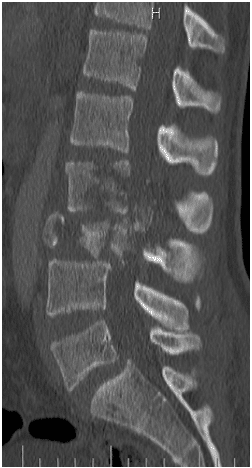

Un chico de 18 años se cayó desde tres pisos. Pérdida casi total de todas las funciones neurológicas por debajo del nivel de lesión con afectación casi total del intestino y la vejiga

El paciente fue operado y el conducto espinal limpiado de todos los fragmentos óseos. La columna vertebral se fijó de lado y la parte trasera para eliminar la inestabilidad.

La paciente fue enviada a un centro de rehabilitación tras la cirugía y se recuperó rápida y completamente en 5-6 meses.